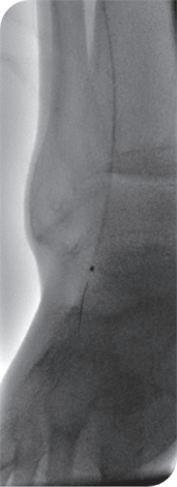

Researchers have shown that quiescentinflow single-shot (QISS) magnetic resonance imaging (MRI) is able to identify more below-the-knee vessel segments than digital subtraction angiography (DSA) in patients with chronic limb-threatening ischaemia (CLTI). Taking first prize for best abstract, Alexander Crichton (Houston, USA and Birmingham, UK) shared this and other findings at the 39th European Society for Vascular Surgery (ESVS) annual meeting (23–26 September, Istanbul, Türkiye).